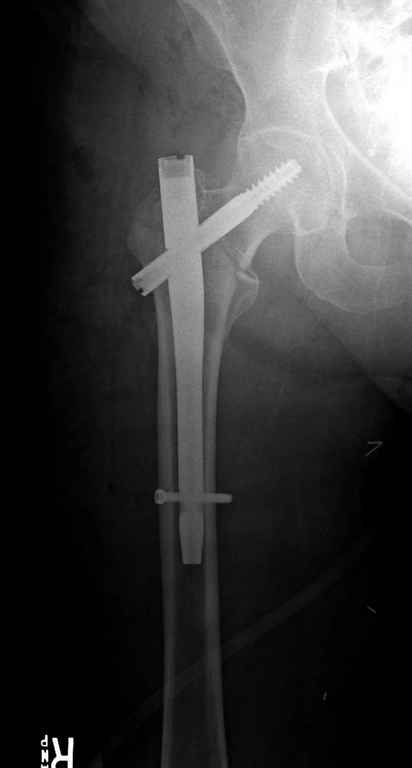

Вашему вниманию представляется похожий случай, пациентке 70, осложнился в течение одного месяца после операции. Ревизия с заменой сустава, кабельная фиксация на трохантер. При установке в дистальном диафизе обнаружен тонкий кортикальный слой и сделана профилактика от возможного перелома аллографтом.